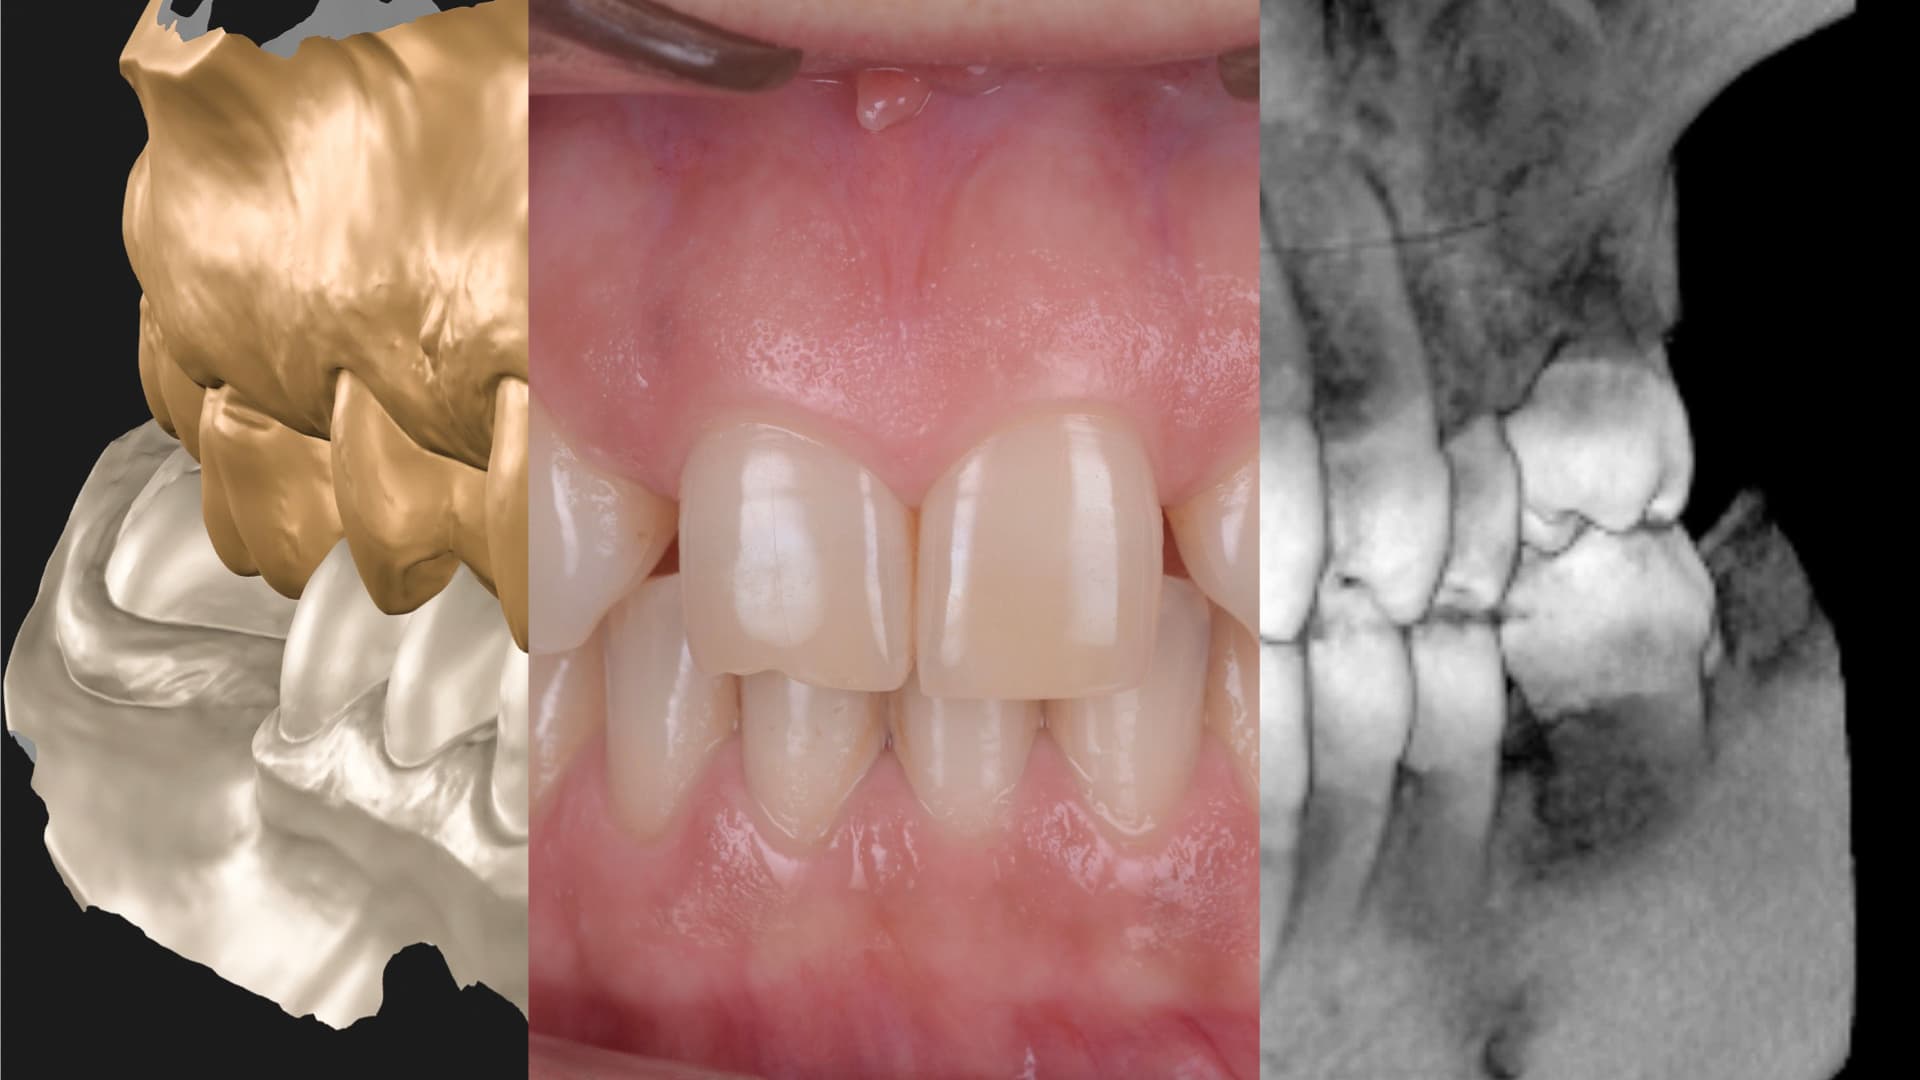

1. Diagnosis and Digital Mapping

Early detection. Full understanding.

We begin with a clinical and radiographic assessment, using 3D scans and digital probes to evaluate pocket depth, bone loss, and gum inflammation. This allows us to grade severity and monitor progression with precision. Most importantly, we assess how the disease affects your overall treatment plan.